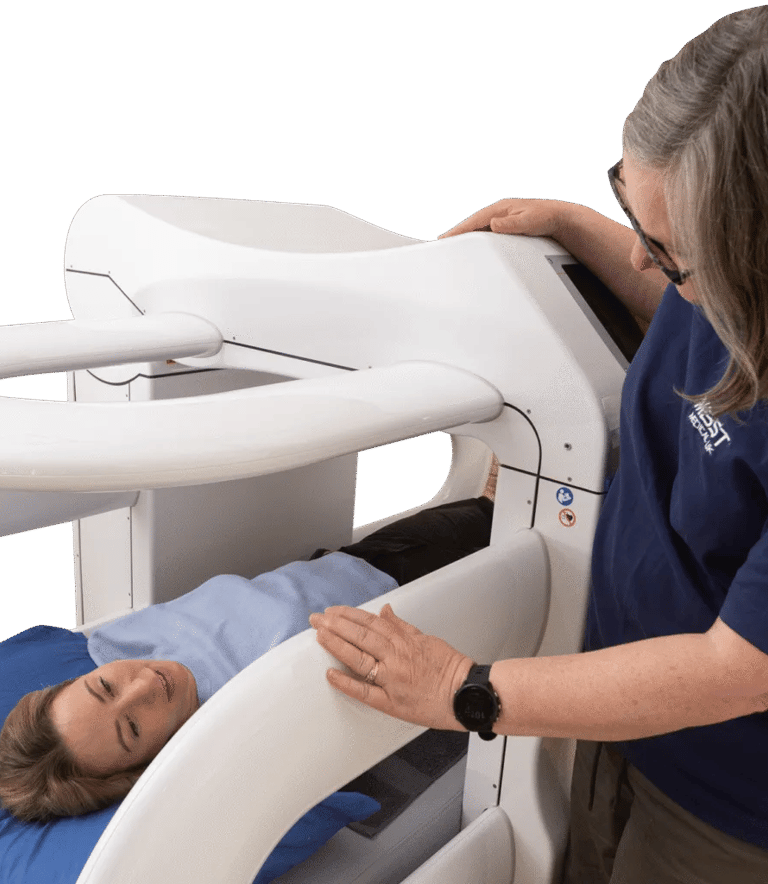

MBST Therapy Advanced Non-Surgical Solution for Joint & Spine Pain

MBST is an innovative German technology that uses therapeutic magnetic resonance to stimulate cell regeneration, repair cartilage, and relieve chronic pain without surgery, injections, or radiation.

Advanced medical technology focused on cellular repair

When pain, stiffness, or injury disrupt your life, real relief should target the source not just cover up the symptoms. MBST offers a different path. By acting directly on the cells where damage begins, it aims to ease pain, reduce inflammation, and improve mobility for people dealing with musculoskeletal issues, chronic discomfort, or long-term conditions.

MBST uses precise magnetic resonance signals to create conditions that support healthy cell activity and natural repair. When cells operate the way they’re meant to, they can better restore balance, regenerate tissue, relieve discomfort, and reduce inflammation.